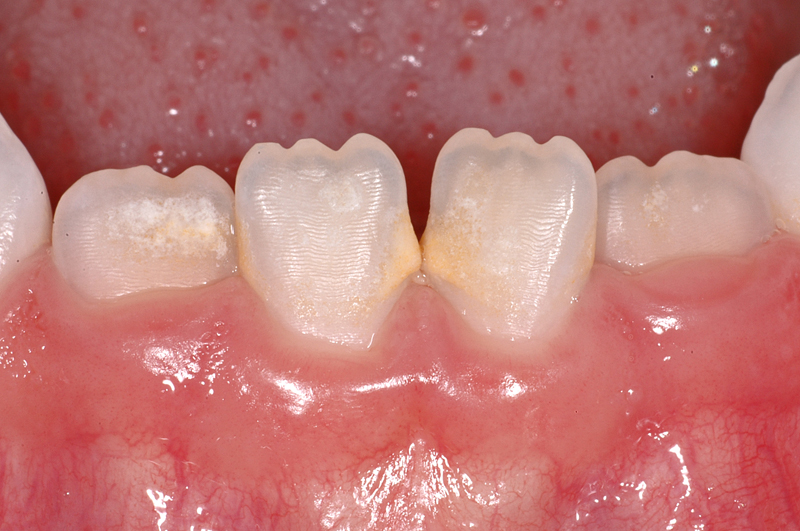

In diesem Beispiel ist ein «weisser» Fleck auf dem rechten oberen Schneidezahn (Zahn 11) einer 7-jährigen Patientin zu sehen. Solche Flecken sieht man häufig, z.B. wenn im Kleinkindalter ein Sturz auf die Milchzähne erfolgt ist und dabei die Wurzeln der Milchzähne die Zellen, die den bleibenden Zahn bilden, in Ihrer Funktion beschädigen. Aber auch andere Ursachen sind möglich, meist lässt sich aber nicht genau sagen, weshalb der Fleck entstanden ist.

Der Zahn ist allerdings, abgesehen von einer ästhetischen «Einbusse», vollkommen in Ordnung und braucht keine Therapie. Ästhetische Korrekturen sind möglich, sie werden individuell nach Bedürfnissen und Möglichkeiten geplant.

Im Bild sind zudem feine Querrillen auf den Zähnen zu sehen. Diese Rillen heissen Perikymatien und sind völlig «normal»

Sie sind vor allem an frisch durchgebrochenen, jungen Zähnen gut sichtbar. Die Ausprägung kann von Person zu Person verschieden stark sein.

Im Laufe des Lebens verflachen und verschwinden diese Rillen meist durch den Verlust von Zahnschmelz.

- Weisser Fleck auf dem rechten oberen Schneidezahn (Zahn 11) einer 7-jährigen Patientin